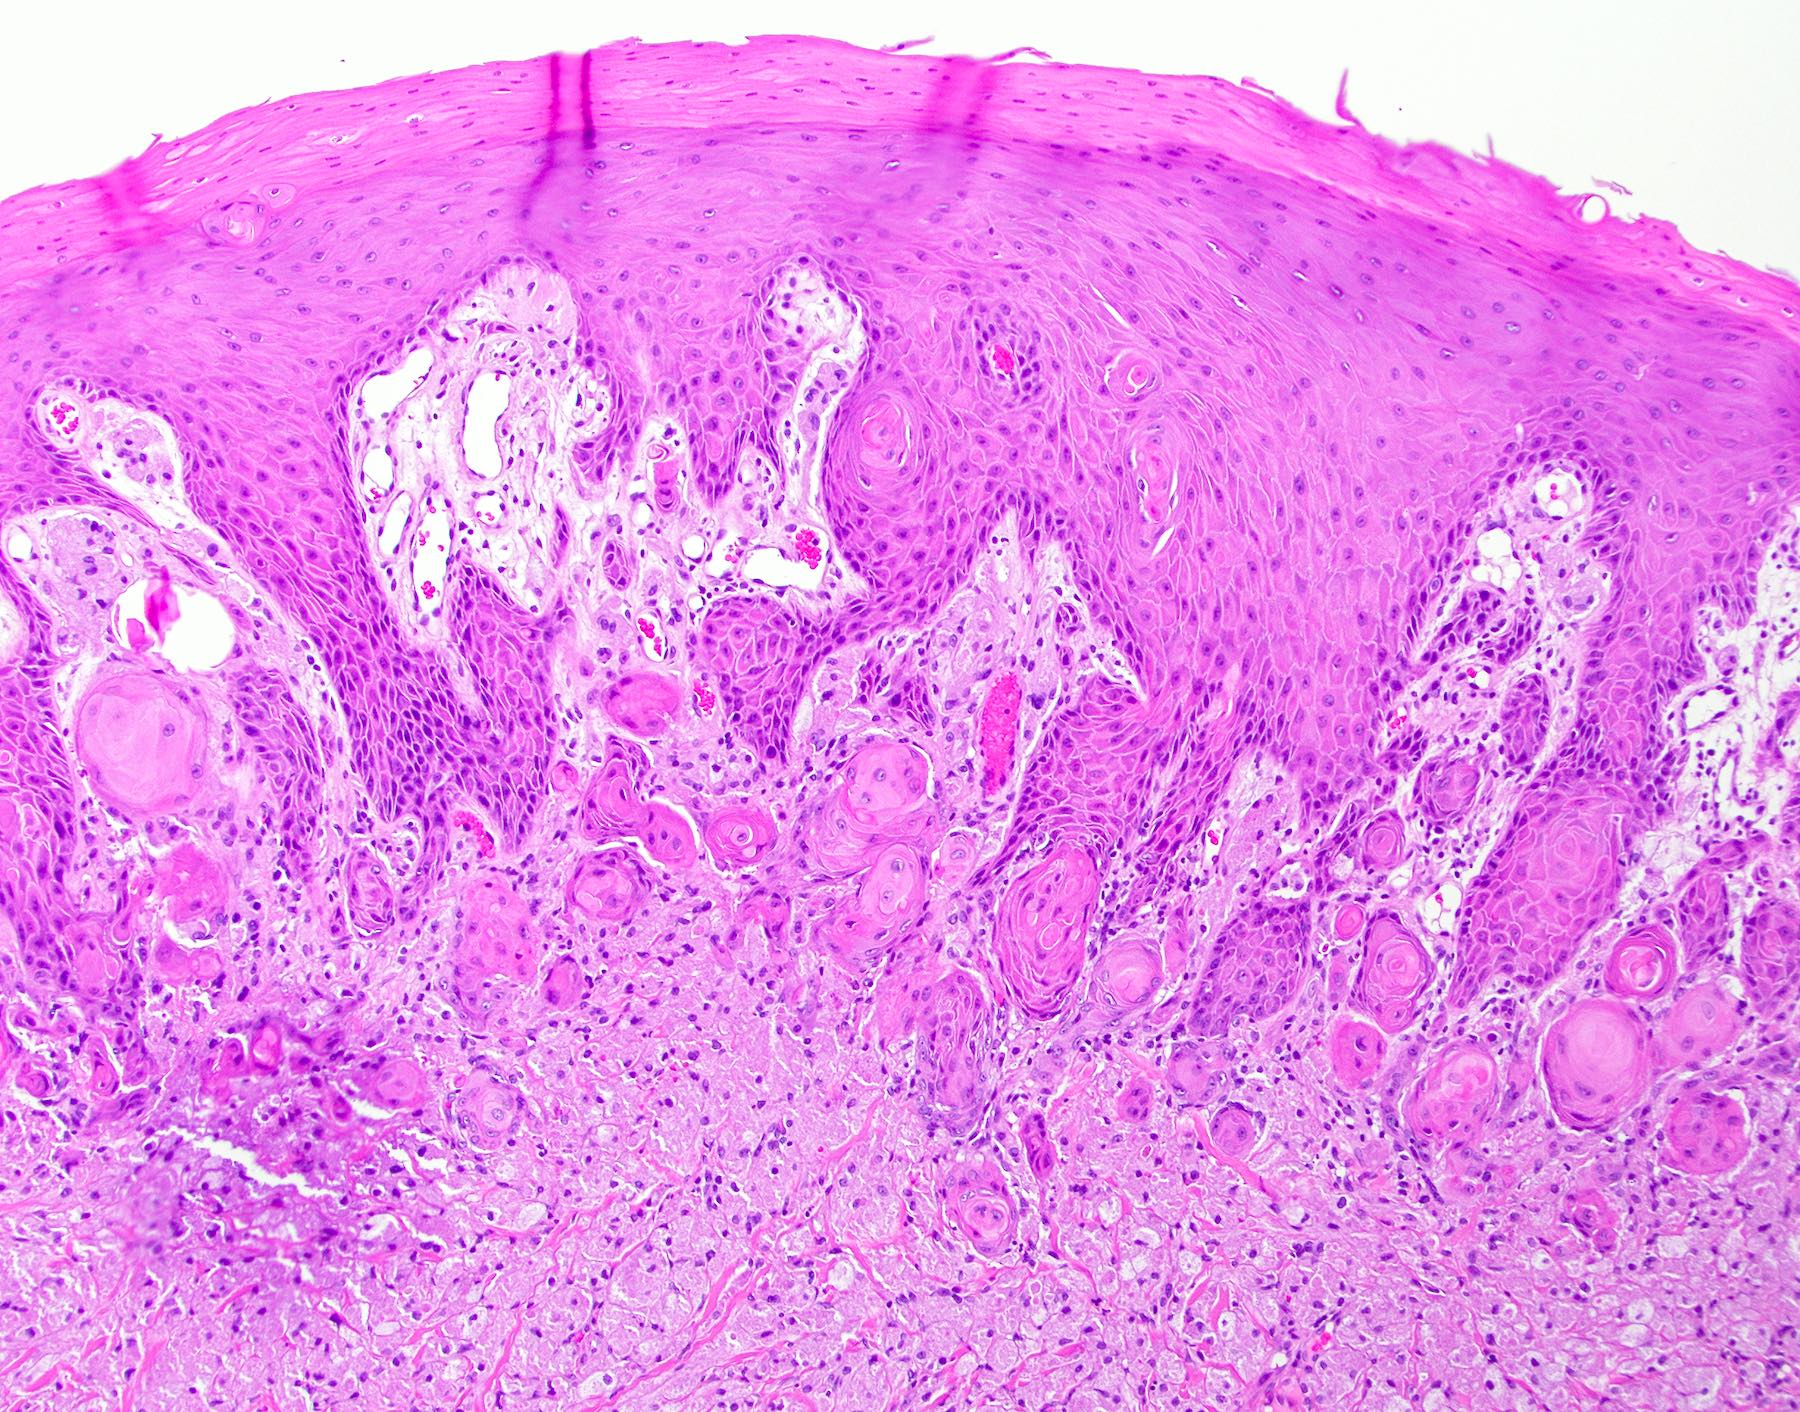

Microscopic (histologic) description

• Thick elongation of the overlying epithelium with bulbous or sometimes jagged / sharp, interconnecting rete ridges (Am J Dermatopathol 2011;33:112)

• May exhibit keratin pearl formation: concentric layers of keratinocytes with central keratinization (Am J Dermatopathol 2011;33:112)

• Lacks significant nuclear atypia; although mitotic figures may be seen, they are not numerous or atypical (Am J Dermatopathol 2011;33:112)

PEH in granular cell tumor PEH in granular cell tumor

PEH in granular cell tumor

The above biopsy was taken from the posterior dorsal tongue at the midline. What is the microscopic pattern of the epithelium called?

1. Pseudoepitheliomatous hyperplasia

2. Squamous cell carcinoma

3. Squamous ductal metaplasia

4. Verrucous carcinoma

Practice answer #1

A. Pseudoepitheliomatous hyperplasia. When combined with the clinical information / photograph, the overall diagnosis of this case is median rhomboid glossitis, which is a particular diagnosis made in a patient with a red patch on the middle portion of the posterior dorsal tongue. The epithelium often shows elongated, bulbous shaped rete ridges (pseudoepitheliomatous hyperplasia) and superficial candidal colonization, as highlighted here by a PAS stain. Answer B is incorrect because the epithelium does not show significant atypia or detached islands of invasive epithelium. Answer C is incorrect because there are no salivary ducts pictured above; however, squamous ductal metaplasia may be seen in association with pseudoepitheliomatous hyperplasia in a setting of necrotizing sialometaplasia, a condition most often diagnosed on the hard palate. Answer D is incorrect because although the epithelium is bulbous and hyperplasic, a prominent verrucoid surface architecture and keratin clefting are not identified.